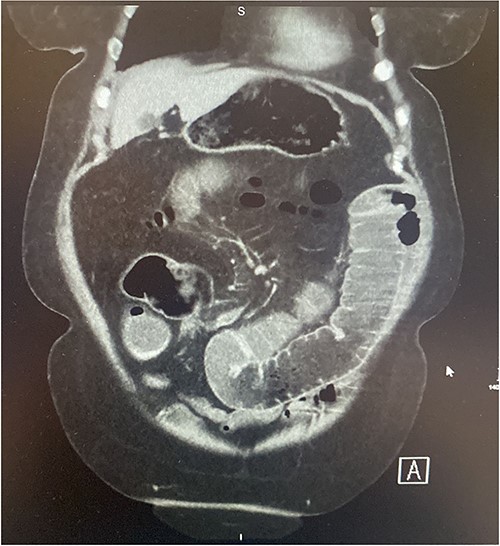

A 73-year-old female presented complaining of acute onset right sided upper abdominal pain associated with three episodes of bilious vomitus and constipation. Clinically, her abdomen was tender, distended, and tympanic with increased bowel sounds. Of note, she described a 3-month history of repeated low grade abdominal pain with vomiting. The clinical picture was concerning for that of bowel obstruction. Contrast enhanced CT scan of the abdomen and pelvis (CTAP) demonstrated multiple dilated loops of small bowel measuring 4.5 cm at their maximum calibre. In the right abdomen there was a focus of ileo-ileal intussusception with a filling defect measuring ~6–7 cm (Figs 1–2). Multiple enlarged enhancing lymph nodes, measuring up to 10 mm, were identified at the level of the intussusception. The duodenum, distal ileum, and jejunum were collapsed.

Coronal section of contrast CT AP demonstrating small bowel intussusception with proximal dilation and associated filling defect.